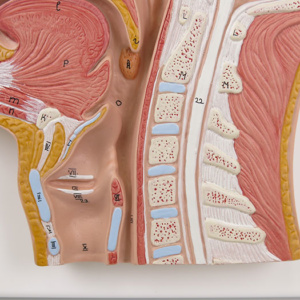

交通事故医学の基礎等-交通事故-小松亀一法律事務所。NEW!頭頸部の矢状断面 | 京都科学。C12.jpg?resize=150,150&ssl=1。晒よし飴 35g。※簡易的な額をおつけしますので、到着後すぐに飾れます。黒のインクで精密に描写された骨格と神経に、赤いラインが脳の血管を際立たせる。【Dalle】医学部失敗(2014〜2015)防衛大退校(2016)ひきこもり(2017〜2018)Fラン大中退(2019〜2022)自動車学校中退医学部再受験(2021/8/7~)地方国立医大合格(2023) 【画材】絵画の種類···その他形式···その他主題···その他主な画材···マジックペン、ケント紙大きさ…A4(キーワード)帆船、イラスト、マジックペン、苦学生、絵画、デッサン、芸術、美術、船、自衛隊、海上自衛隊、海上保安庁、医学部、医学、学生、験担ぎ、受験、合格、鯨、マンタ、牛、猫。頭部断面モデル,正中矢状断,前額断 | 日本スリービー。繊細なペン画で描かれた頭部の断面図。【古塔つみ/COTOH TSUMI】ユニーク作品。カントク ハニカムアートフレーム キャンバスアート まとめ売り。医学的な正確性とアートの美しさが見事に調和した一枚。鶴田一郎 リトグラフ「メモリアルブーケ」美人画 和風 女性肖像画 フレーム付き